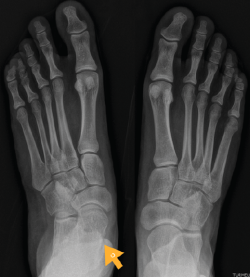

Figura 7. Radiografía del segundo caso: sinostosis talocalcánea media en ambos pies.

Segundo caso (Figura 7)

Se trata de una paciente mujer de 18 años de edad, higienista dental, sin antecedentes patológicos de interés, que presenta pies planos valgos bilaterales dolorosos, el derecho de 23° y el izquierdo de 21° de valgo, por sinostosis calcaneoastragalina media en ambos pies. En ella observamos básicamente una clínica de dolor en el seno del tarso, con déficit de movilidad de la articulación subtalar en ambos pies. Se realiza estudio mediante radiografías de los pies y los tobillos en carga y TAC de ambos pies (afectación bilateral). Radiológicamente, las articulaciones tibioperoneoastragalina y subtalar están preservadas. Se diagnostica de coalición tarsal de tipo 4 de la clasificación de Rozansky(26). El balance articular es de: flexión = 45°; extensión = 20°; inversión = 0°; eversión = 0°. La escala de la AOFAS para el tobillo derecho presentaba una puntuación de 62 (20-37-5). Los ángulos radiológicos iniciales son: Moreau-Costa-Bartani interno = 141°; declinación talar = 18,4°; Meary = 6,3°; Kite = 25,6°; taloescafoideo = 48,3°.